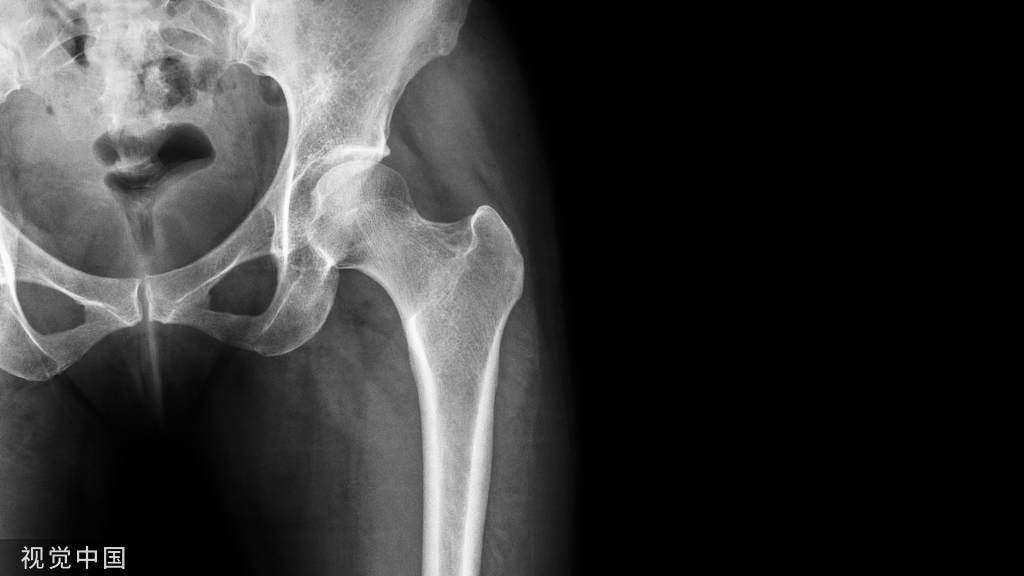

是关节内慢性滑膜化生,生成软骨结节肿块。这些软骨小体可能从滑膜上分离下来,然后在滑液里独自生长,他们可能随后重新附着在滑膜上,变成血管化、钙化或骨化(骨软骨瘤病)。临床特点是明显的软组织肿块,关节疼痛,关节活动受限,这些可能暗示囊肿或软组织新生物。

MRI表现:诊断一般通过常规X线摄片,显示未多发关节内骨化小体,MRI上滑膜骨软骨瘤病表现为多发低信号结节,偶尔包括高信号的骨髓脂肪,相关滑膜不同数量的结节状增厚。虽然未钙化的滑膜软骨瘤在平片上不能直接显示,但在MRI上可看到关节内囊肿或局限性环节积液,因为化生软骨的信号由其内含的自由水质子决定。